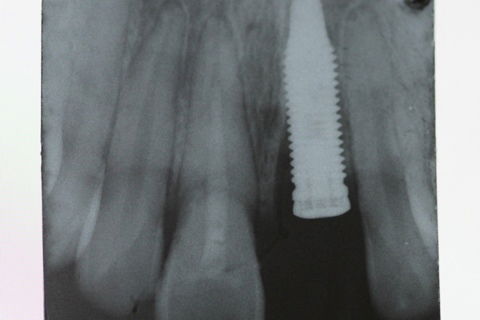

Após o diagnóstico, foi tomado como conduta a exodontia do elemento 21(devido a fratura radicular) e a instalaçāo do implante imediato a fim de preservar a região da estética vermelha e papilas interdentais. Por ter sido realizado um tratamento de urgência e com tempo limitado para planejamento foi escolhido um implante com conecção HE da marca TITANIUMFIX de plataforma regular 3.75 x 15 mm na região do 21 e tratamento de urgência endodôntica no elemento 11 e confecção dos provisórios em resina composta aproveitando os fragmentos dos elementos como mostra nas FIGURAS 3, 4 E 5.